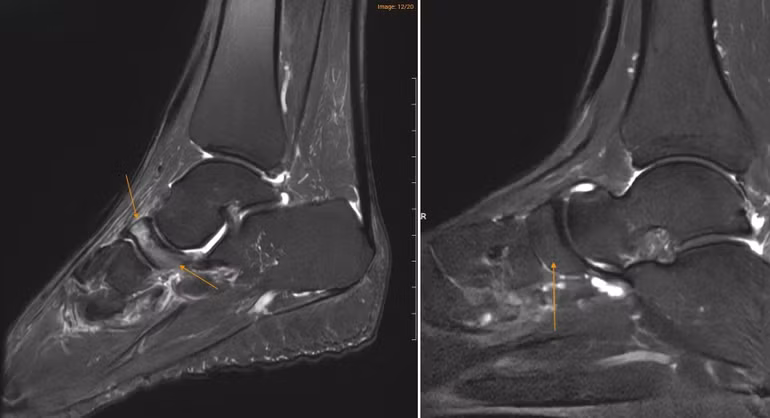

Tại Medlatec, bác sĩ đã chỉ định chụp cộng hưởng từ (MRI) để tìm kiếm những tổn thương sâu trong cấu trúc xương. Trên lát cắt Sagittal T1W, hình ảnh cho thấy xương ghe bị xẹp và biến dạng điển hình hình dấu phẩy, kèm theo tình trạng đặc xương dưới sụn. Trên chuỗi xung T2W FS, ghi nhận tình trạng phù tủy xương ghe rõ rệt.

Hình ảnh MRI cho thấy xương ghe ở bệnh nhân mắc Hội chứng Müller–Weiss (bên trái) có vùng sáng hơn bất thường, trong khi xương ghe ở bàn chân bình thường (bên phải) có hình ảnh đồng nhất hơn.